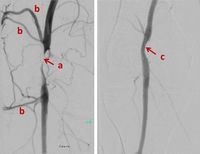

Percutaneous Transluminal Angioplasty (PTA) of the superficial femoral artery (SFA). Left image: subtotal calcified occlusion a) with many collaterals b); Right image: good patency after ballon PTA

Interventional procedures using ionising radiation have revolutionised medicine in the past few decades for therapy and palliation, resulting in more patients being offered treatments that would not have been possible before with more invasive open surgery. The vast majority of interventional procedures are performed as “minimal invasive percutaneous therapies”.

As technology continues to advance, interventional procedures become more complex and some may take several hours to complete. New technologies with smaller catheters, guidewires, stents, filters and many other devices also present new challenges for radiological protection, such as aortic stent grafts, cardiac valve replacement, prostate embolisation, thrombus aspiration after stroke or selective internal radiation therapy (SIRT).

Physicians, assisted by nurses and radiographers, perform X-ray guided interventions as an alternative to conventional surgery. Most of these interventions are less invasive, the recovery periods are shorter, and for many types of interventions the complication rate is lower. In addition, some patients who may not tolerate anaesthesia and conventional surgery, as well as lesions that were not previously accessible, can now be treated by less-invasive image-guided interventions. In addition, interventional procedures offer new therapies where options of other medical specialties do not exist, such as embolization of liver tumours with chemical drugs or radioisotopes (SIRT).

Interventions are usually guided by fluoroscopy. Radiographic cine series or stored images from fluoroscopy are taken to document the outcome of diagnosis or treatment. Interventions can also be guided by computed tomography (CT) imaging, with images taken while the interventionalist steps behind a shield or out of the room, or by CT fluoroscopy, in which the interventionalist stays at the patient for obtaining images during device manipulation.